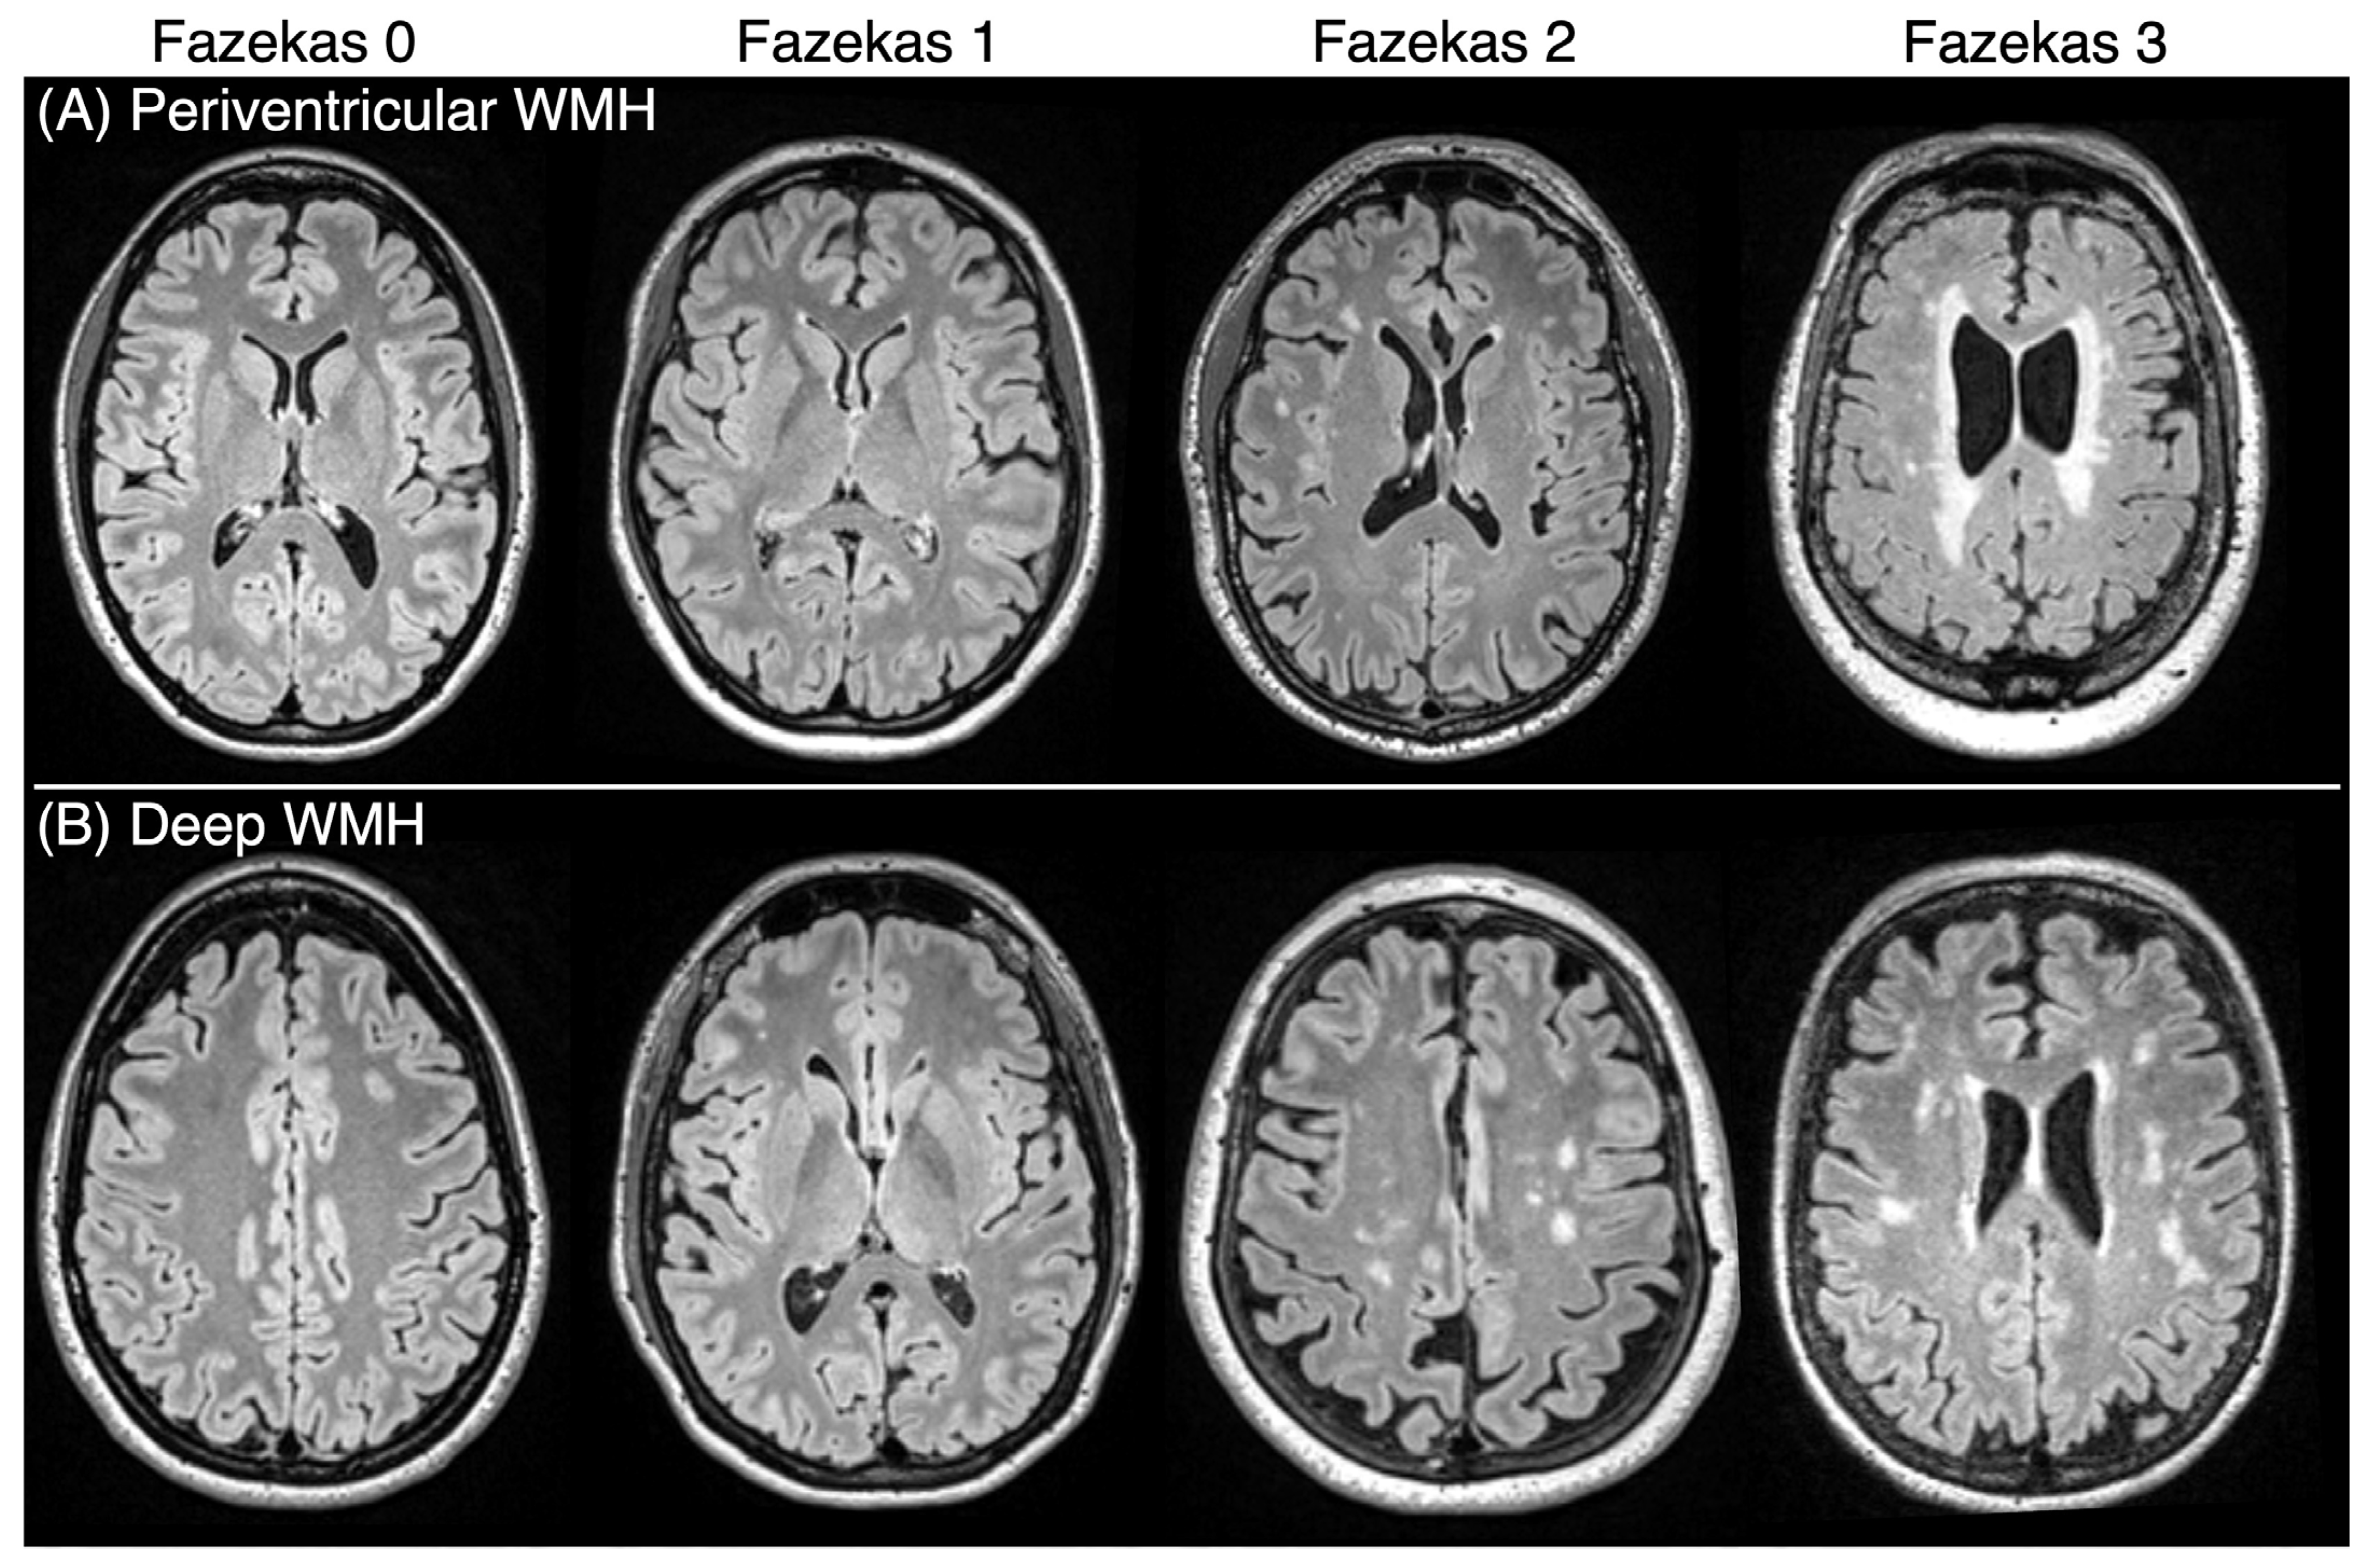

- Fazekas, F.; Chawluk, J.B.; Alavi, A.; Hurtig, H.I.; Zimmerman, R.A. MR signal abnormalities at 1.5 T in Alzheimer’s dementia and normal aging. Am. J. Roentgenol. 1987, 149, 351–356. [Google Scholar] [CrossRef] [PubMed]

| Fazekas Score Total | 2.55 (1.63) |

| Fazekas Score Deep | 1.08 (1.07) |

| Fazekas Score Periventricular | 1.47 (0.76) |